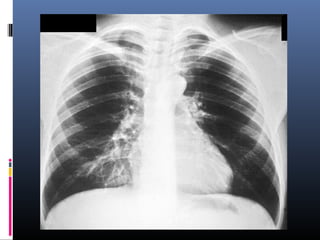

NEUMONIA POR LEGIONELLA PNEUMONIA O

“ENFERMEDAD DE LOS LEGIONARIOS”

 Neumonía atípica con fiebre alta, gran postración, síntomas

abdominales y tos no productiva, asociada a dolor pleurítico.

 Radiológicamente presenta infiltrados bilaterales

confluentes.

 Diseminación local.

 Afectación lobar frecuente.

 Derrame pleural más del 50 % de los casos.